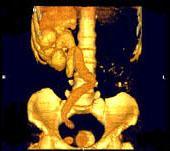

问题 男,33岁,反复尿频,尿急,尿痛3年余,排尿困难4个月,尿常规:蛋白(+),红细胞01/HP,白细胞(++),CT扫描图,下列诊断哪项说法正确 ( )

选项 A、双侧肾积水,双侧输尿管扩张 B、膀胱多发性假性憩室 C、膀胱慢性炎性肉芽肿 D、膀胱癌 E、膀胱结石

答案 ABCE